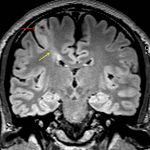

- T2/FLAIR signal hyperintensity in the right precentral gyrus (including the hand motor knob) and extending slightly into the postcentral gyrus with blurring of the gray-white interface

- Band of T2/FLAIR signal hyperintensity bridging this abnormal cortex and the ventricular ependymal margin

- No substantial gyral expansion or intracranial mass effect

Focal cortical dysplasia (type II)